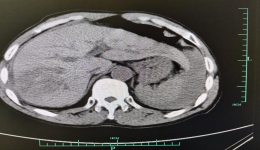

我院外四科是集普外科、胸外科、泌尿外科、小儿外科等专业的医疗、教学、科研为一体的综合外科专业科室,拥有一支高水平的医疗服务队伍,近年来,在陈刚教授的带领下,完成了数例高难度骑跨颈胸部和胸腹部肿瘤的手术,运用以外科为主的手段挽救了多...